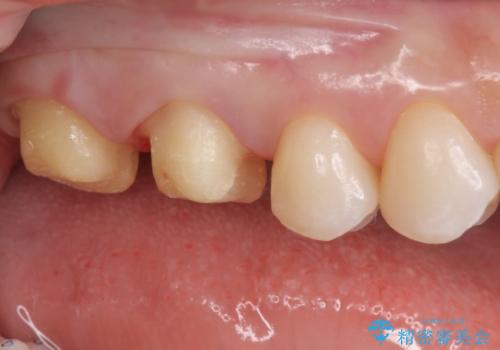

- 銀歯を白くしたいとのことで来院されました。

詰め物が覆っている面積が大きいため、強度を考慮してセラミックインレーではなくクラウンでの修復処置を進めていきます。